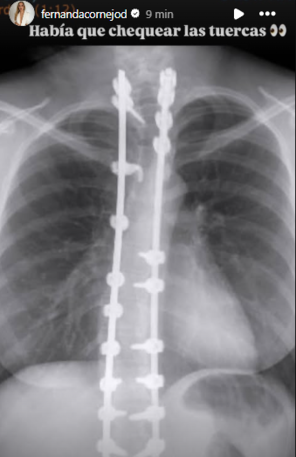

De hecho, Fernanda Cornejo subió durante el lunes una imagen a sus historias de Instagram, en la que se ve una radiografía de su espalda.

Allí, se aprecian las prótesis y pernos que tiene tras someterse a la compleja cirugía por su escoliosis idiopática.

“Había que chequear las tuercas”, escribió brevemente Fernanda Cornejo junto a la imagen, dando cuenta que todo estaba bien después de años de la intervención.